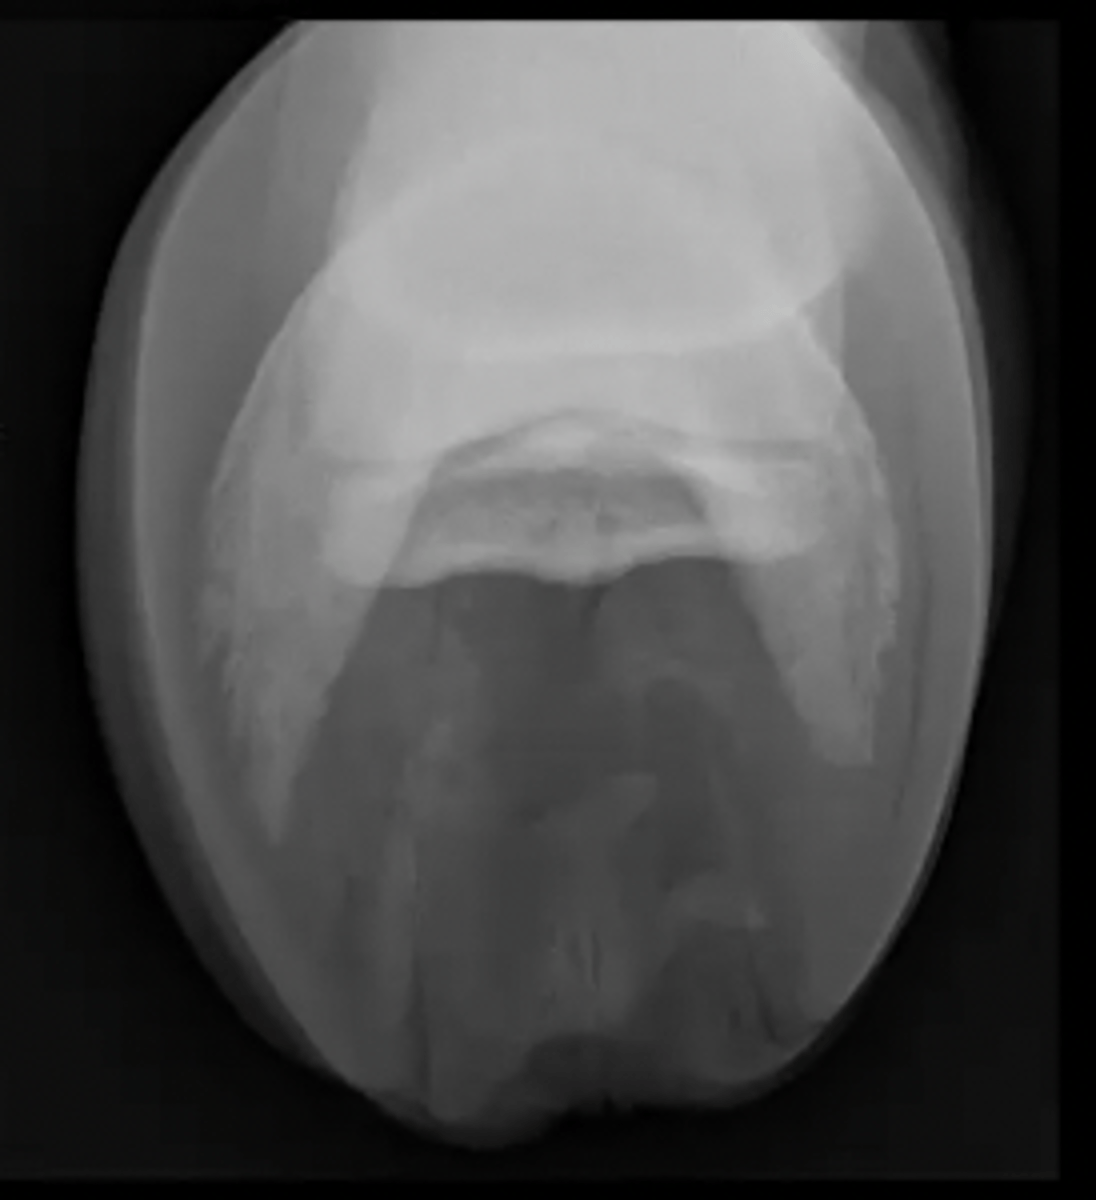

navicular flexor skyline view

What special equine view is this?